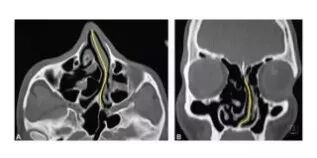

CT显示扭曲的鼻中隔(黄线)使经鼻气道不畅,多源于面部撞击伤。